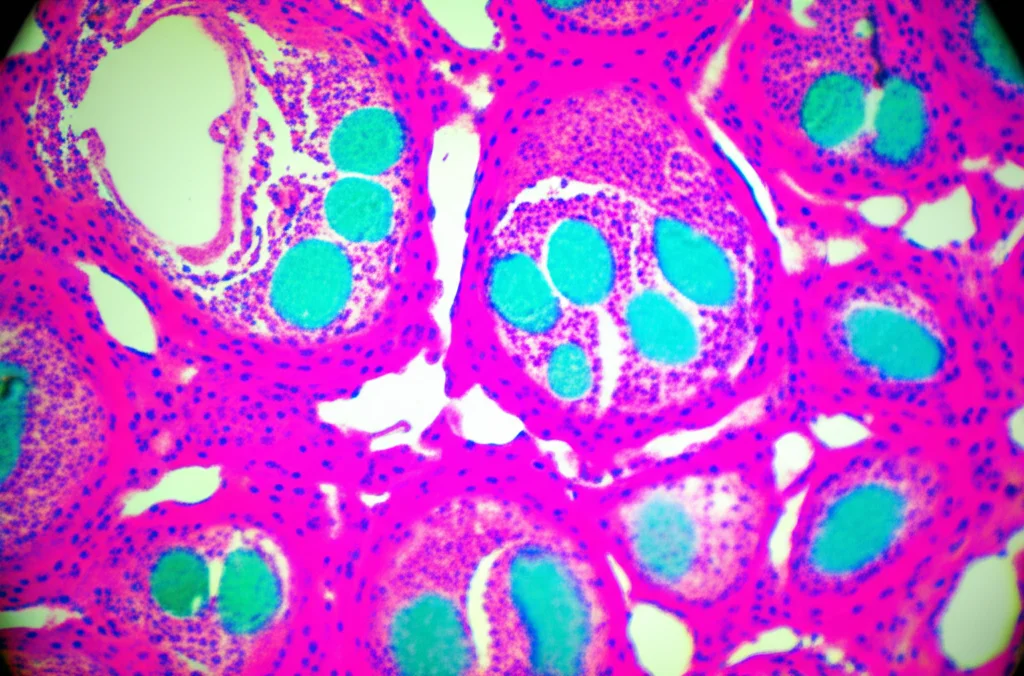

- La risposta del tumore al trattamento neoadiuvante, valutata al microscopio sul pezzo operatorio (TRG rating).